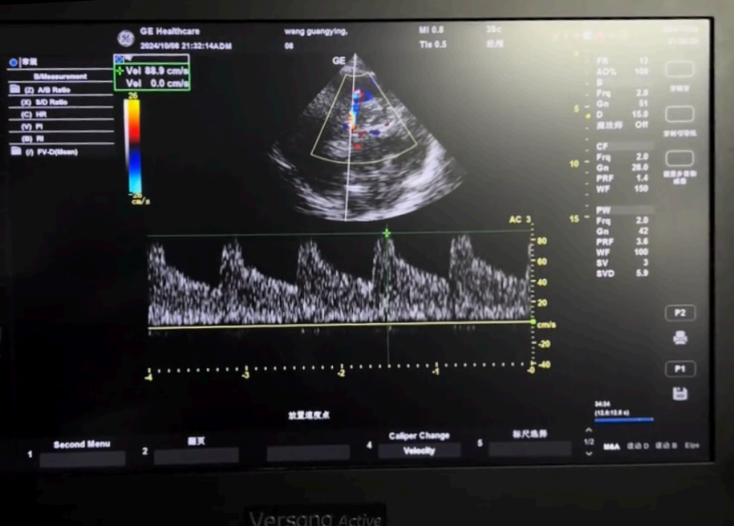

圖4:?腦中動(dòng)脈(MCA)?流速:評(píng)估腦?流(操作者:吳威)